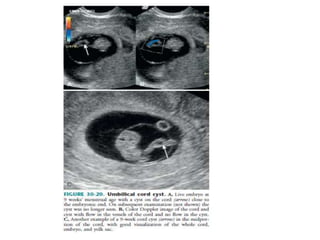

5.UMBILICAL CORD AND CORD CYST

 Formed at the end of the sixth week.

 Contents : all of which are embedded in

Wharton’s jelly.

Two umbilical arteries

single umbilical vein

allantois

Yolk stalk

 Cysts and pseudocysts within the cord occur

in first trimester.

 Seen usually in 8th week and disappear by 12th

week.

 Singular, with a mean size of 5.2 mm.

 Originate from the remnants of allantois or

yolk stalk and have an epithelial lining.

 If seen in 2nd and 3rd trimester they are

associated with chromosomal abnormalities.